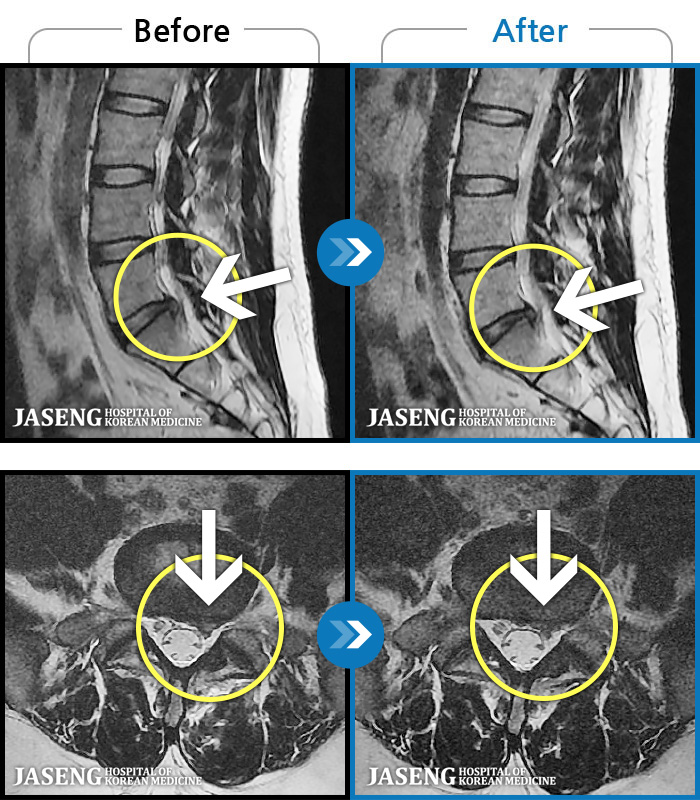

ȯںп Ǹ ǿ ԿǾ, ο ġ ۿ Ƿ ġḦ Ͻñ ٶϴ.